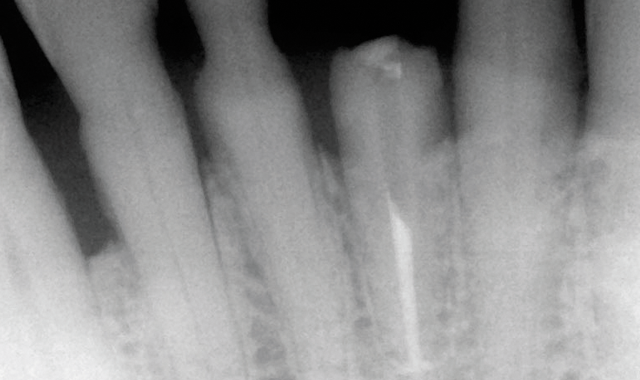

root surface of the lower incisors-which was visible on the radiograph (Fig. 3)-is known as “Riffle-ization.” Described by Dr. Riffle as a technique for removing every last bit of calculus during repeated root scaling, what is now known as “Riffle-izing," ultimately-over the years-changes the shape of the neck of the tooth to resemble an hour glass.

Therefore, based on the clinical and visual evaluation, the preferred treatment would be to restore the fractured #25 with a post and crown and four splinted crowns to restore the anatomy of the four incisors and increase their resistance to both mobility and fracture.

Fig. 3